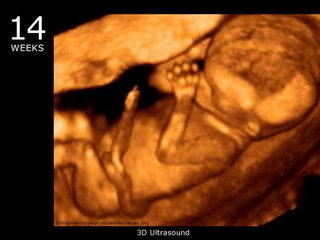

23 haftalık gebelik, hamileliğin ikinci trimesterinin sonlarına yaklaşıldığı bir dönemi ifade eder. Bu süre zarfında, hem anne hem de bebek için birçok önemli gelişim ve değişiklik yaşanmaktadır. Bu makalede, 23 haftalık gebelik dönemindeki fiziksel ve duygusal değişimlerin yanı sıra, bebeğin gelişimi, anne adayının sağlığı ve dikkat edilmesi gereken hususlar ele alınacaktır. Bebeğin Gelişimi23 haftalık gebelikte bebek, hızla büyümeye devam etmekte ve birçok önemli gelişim sürecinden geçmektedir. Bu dönemde, bebeğin gelişimiyle ilgili bazı önemli noktalar şunlardır: